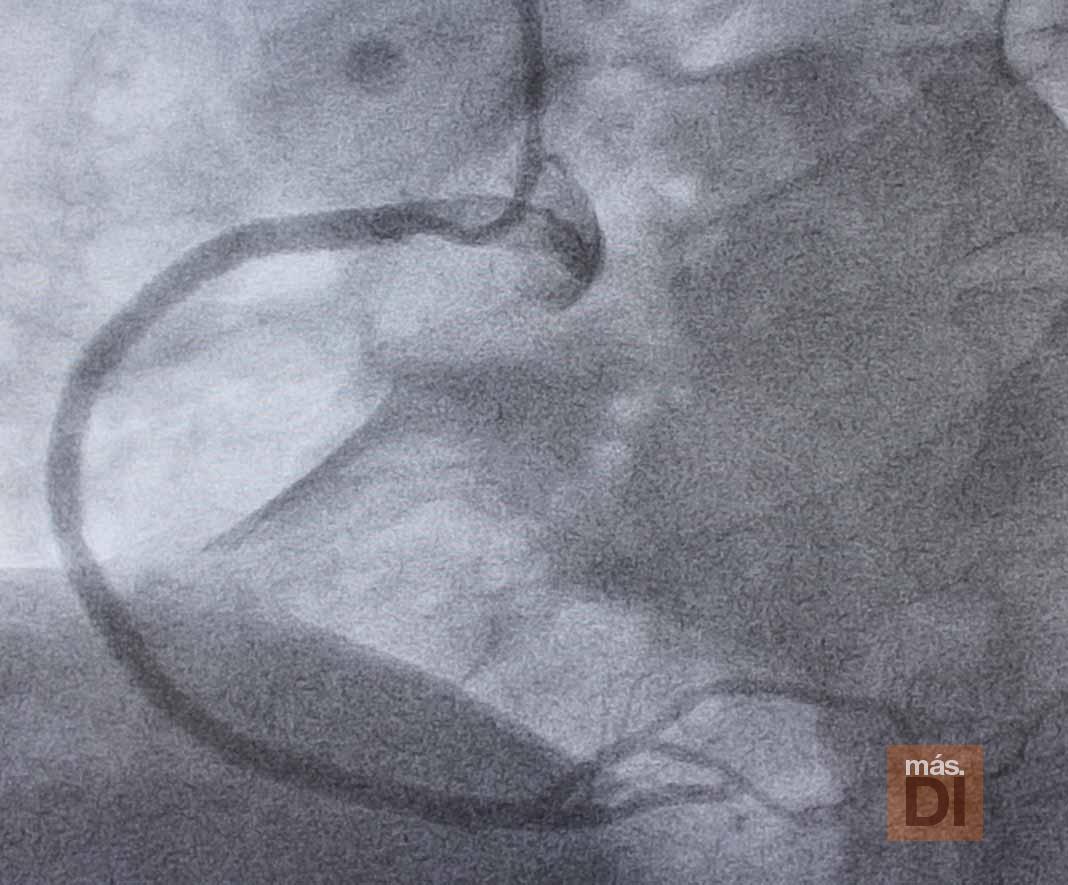

Una vez llega la ambulancia a la Policlínica, el paciente es trasladado directamente a la sala de hemodinámica, donde se le realiza el cateterismo cardíaco que finalmente logrará la apertura del vaso responsable del infarto en un plazo de 20-30 minutos y, según el caso, se implantará un stent coronario (un pequeño tubo de malla de metal) que mantendrá la arteria abierta.